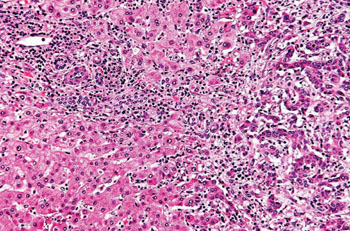

Before delving into the preventive measures, it is essential to understand the nature of Klatskin tumors. These tumors arise from the bile ducts, which are the vessels that transport bile from the liver to the small intestine. The bile ducts can be found inside the liver (intrahepatic) or outside the liver (extrahepatic), and Klatskin tumors typically occur at the junction of the left and right bile ducts where they meet to form the common bile duct.

Klatskin tumors account for about 10-20% of all cholangiocarcinoma cases, which is a rare type of cancer. Due to their location, these tumors can be difficult to treat and are often diagnosed at later stages, which complicates treatment options and significantly affects the prognosis.